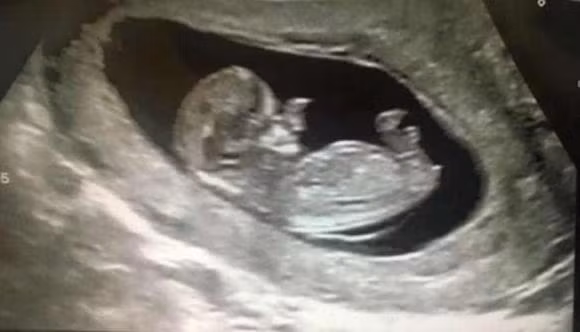

Năm đó, mẹ bé là Amy Poole nhận tin sốc khi mang thai lần hai. Ngay khi siêu âm, bác sĩ đã nhìn thấy điều gì đó bất thường trên khuôn mặt của cậu bé.

Trong quá trình chụp cắt lớp xuyên suốt 20 tuần, bác sĩ thấy rằng con trai của Amy có mô mềm phát triển khó kiểm soát xung quanh vùng mũi. Amy biết rằng con trai mình sinh ra sẽ không giống những đứa trẻ bình thường khác, nhưng thực tế tàn khốc hơn rất nhiều so với những gì cô tưởng tượng.

Qua siêu âm, dị tật ở mũi của cậu bé Ollie đã được đoán trước phần nào.